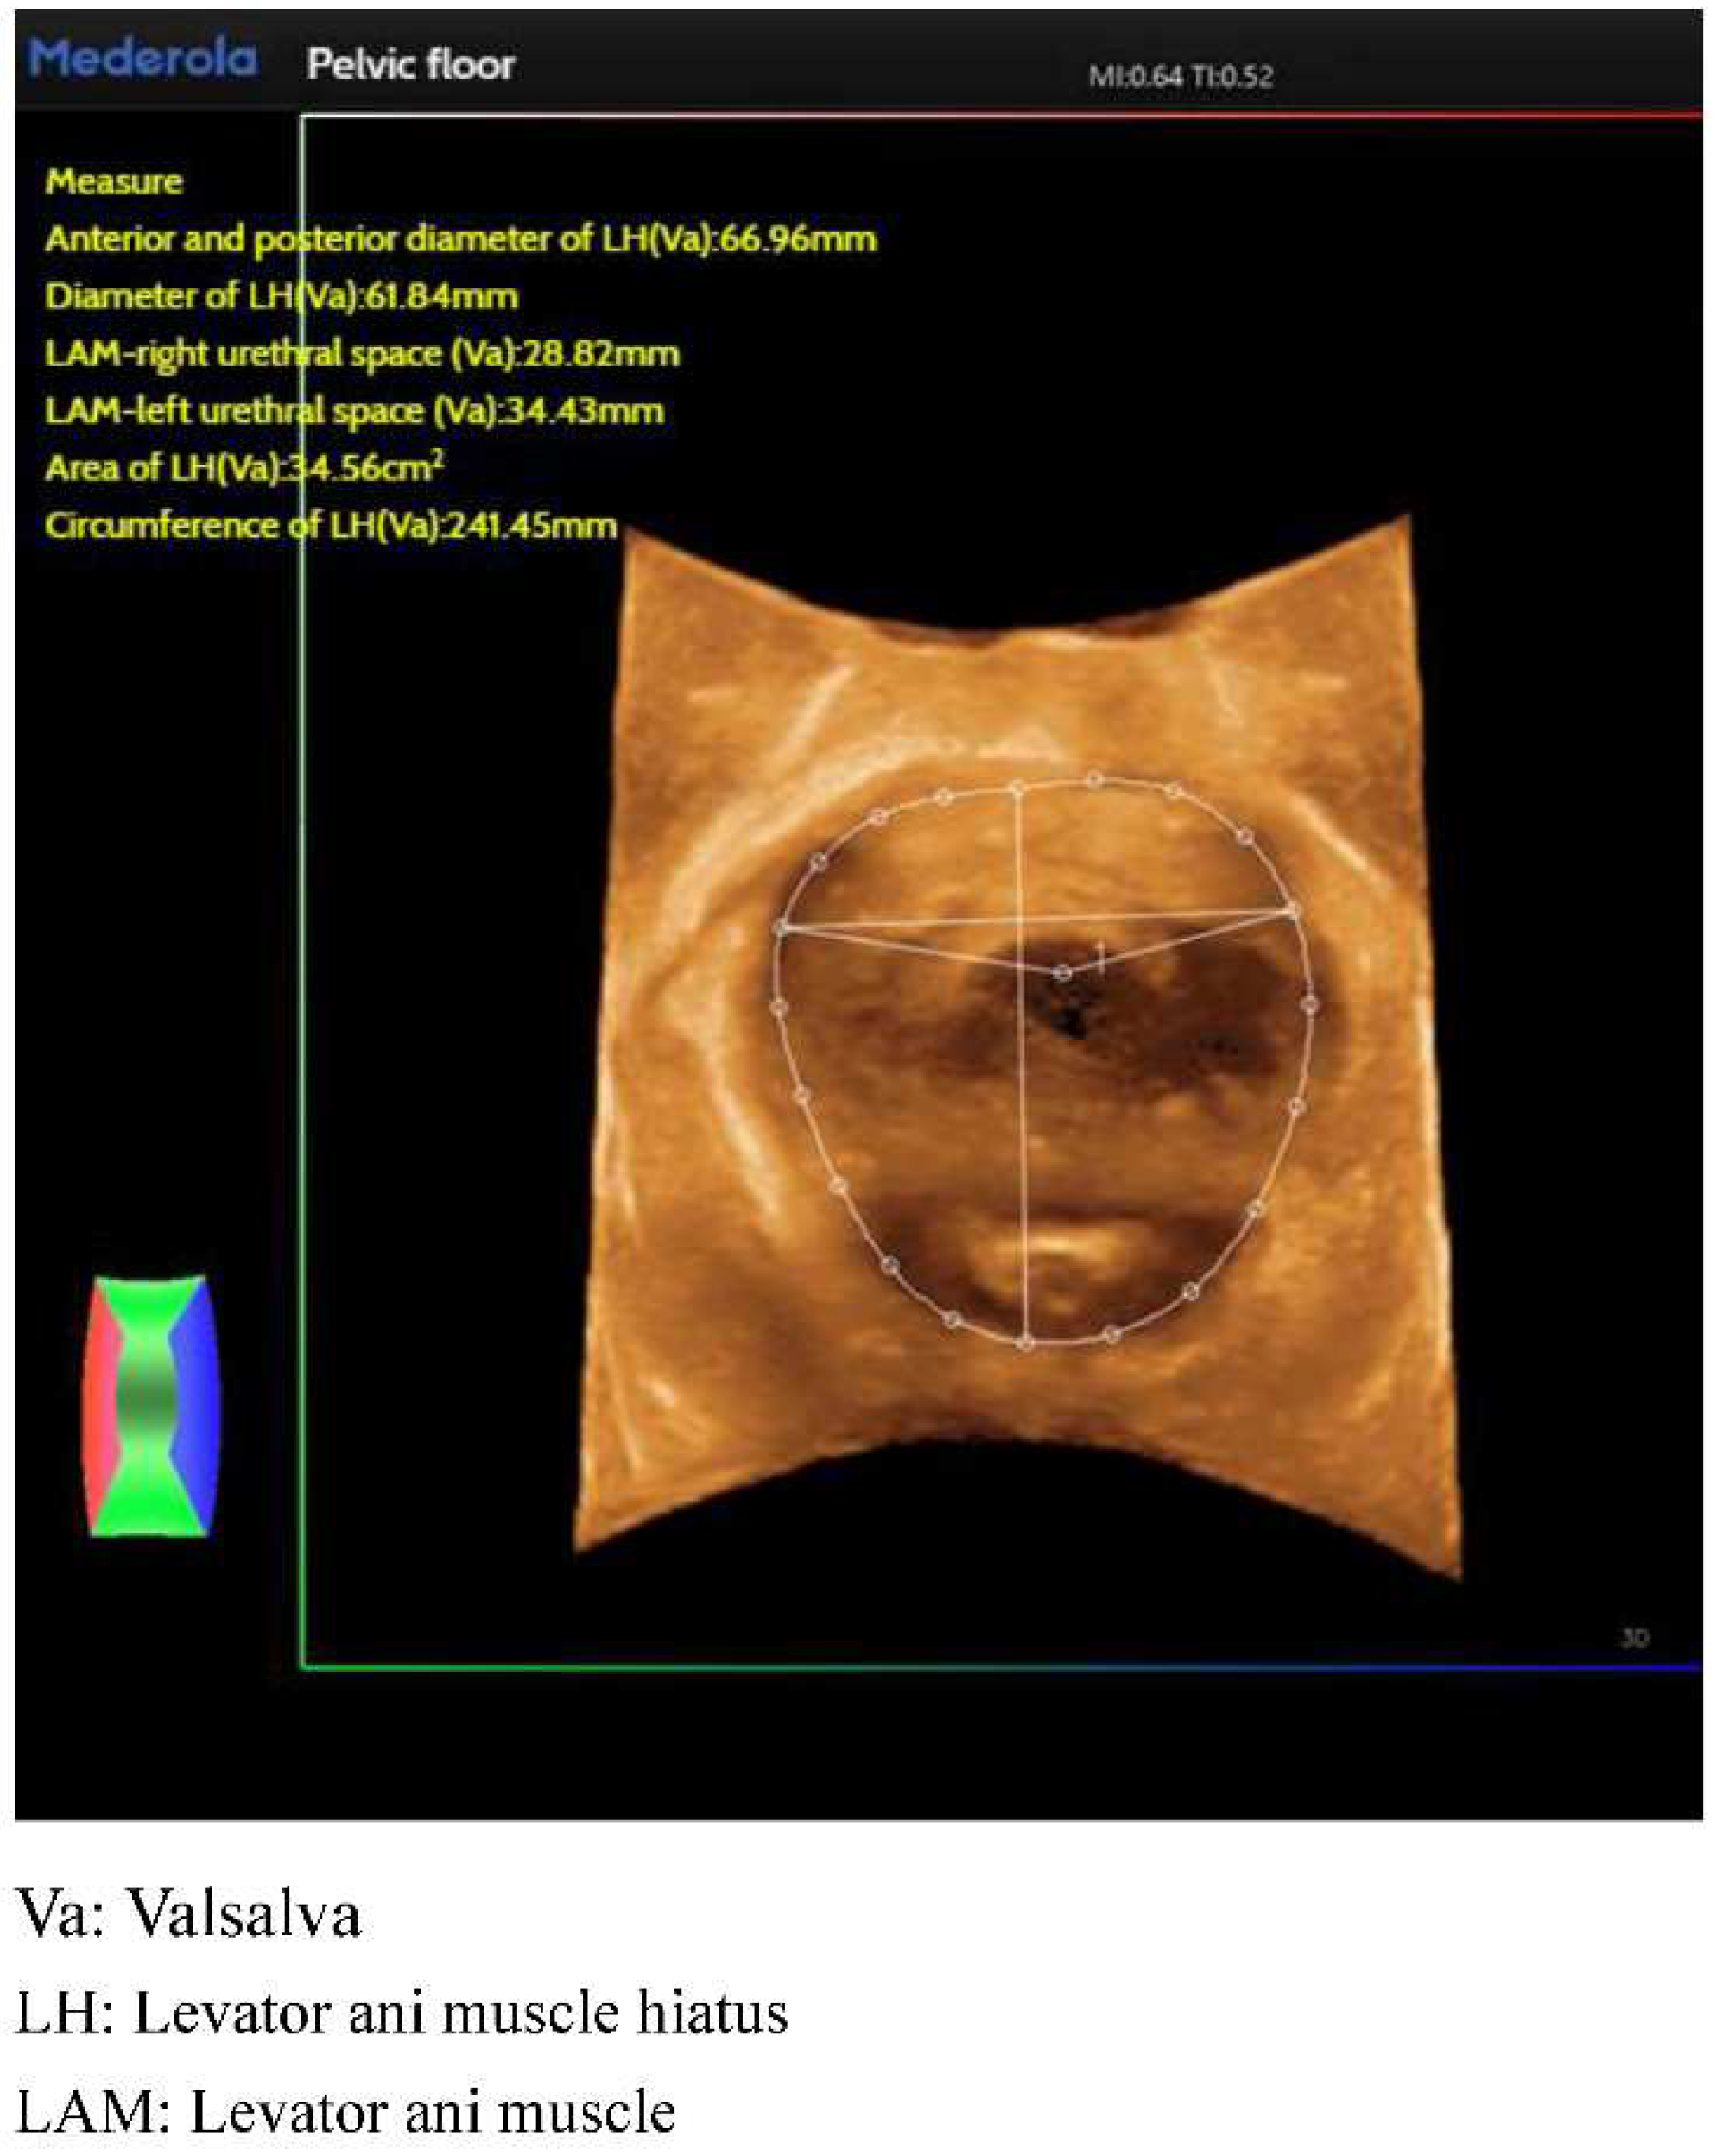

Conventional pelvic floor ultrasound assessment of female pelvic floor structure and function relies on the three dimensions of pelvic floor median sagittal section at maximal Valsalva state, tomographic ultrasound imaging of the anal raphe and anal sphincter and anal raphe fissure at maximal Valsalva state; however, the manual identification is highly empirically dependent, and AI automated identification and measurement can reduce the empirical dependence of the manual identification. The software/algorithms are used to extract features from the labeled images to enable automatic computer recognition. Currently, AI can be used in ultrasound applications to automatically measure and recognize some of the data of pelvic floor structures. For example, in anterior pelvic measurement, the main parameters of the bladder neck in the resting state, including bladder neck distance, bladder posterior angle, urethral inclination angle, etc., are automatically measured, and the above parameters are measured synchronously in the Valsalva state, so as to calculate the angle of rotation of the urethra and the degree of movement of the bladder meridian, etc., and to automatically obtain the bladder bulge and the biological indicators related to stress incontinence, so as to reduce the reliance on the operator’s experience, and to obtain the standardized section and measurement value quickly. The standardized cut surface and measurement value can be obtained quickly by reducing the operator’s experience. (Figure 2). For the anorectal fissure, biological measurements of anorectal fissure dilatation and anorectal muscle damage were automatically obtained by localizing the level of the anorectal fissure in the maximal Valsalva state (Figure 3). For automatic localization of the TUI tomography of the anal retinaculum muscle, operator experience dependence was reduced, and standardized views of the integrity of the anal retinaculum fissure were automatically obtained (Figure 4). Automatically obtained parameters of interest include bladder neck mobility, anal reticulum fissure, urethral rotation angle, and posterior vesicourethral angle, which greatly reduces measurement discrepancies due to physician experience.